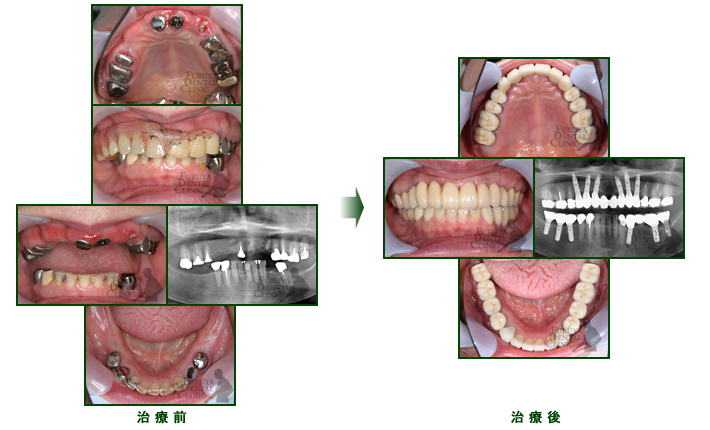

40代 女性

奥歯の入歯で我慢していましたが噛めないし、前歯が異常にすり減ってきたので全顎的治療を施しました。

20代の口腔内よりよくなったと喜んで頂いています。